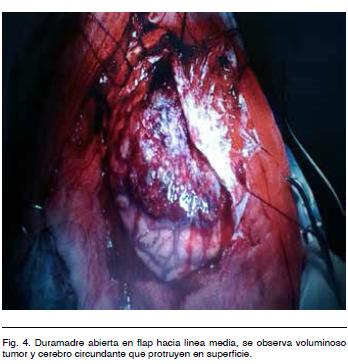

Se realizó tratamiento quirúrgico por abordaje bicoronal con exposición del seno longitudinal superior. Se hizo una exéresis tumoral macroscópicamente completa con plastia de duramadre (Figuras 3, 4 y 5).